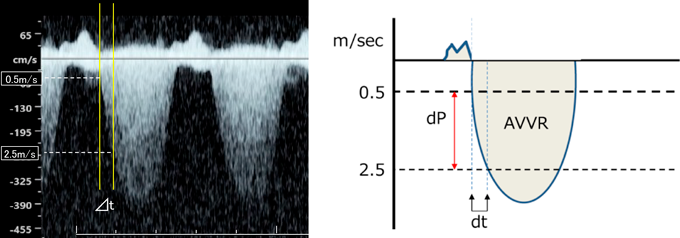

2.3 dP/dt

dP/dtは,心室内圧の時間変化曲線の一次微分関数(傾き)で,その最大値max dP/dtは通常は等容収縮期に得られ,後負荷の影響を受けにくい心室収縮機能の指標となる9).心室収縮機能が良好であれば心室圧は急速に上昇するため高値となる.心エコーでは,これを房室弁逆流の連続波ドプラ波形の立ち上がり速度の時間変化から簡易ベルヌーイ式を基に算出し,収縮機能の指標の一つとしている.出生後の心エコーでは房室弁逆流血流速度が1→3 m/sまで上昇するのにかかる時間から算出されるが,胎児心エコーでは,房室弁逆流血流速度が0.5→2.5 m/sまで上昇するのにかかる時間をdtとし,dPは簡易ベルヌーイ式を用いて(2.5)2×4−(0.5)2×4=24 mmHgであるので,そこからdP/dtを算出する(Fig. 5).800 mmHg/sec以下は低値で,400 mmHg/sec以下は重度の収縮機能低下と考えられる5).なお,dP/dtは最大値が心室収縮機能の指標となるが,胎児では心室圧が低いため,2.5 m/sでも血流波形のピークに近く,流速の増加率が低下している部分にあたる場合には正確な収縮機能を反映しない結果が算出されてしまうため,1→2 m/sで計測するなどの工夫が必要であるが,計測の誤差が大きくなる可能性がある.

Pediatric Cardiology and Cardiac Surgery 41(1): 11-19 (2025)

Fig. 5 房室弁逆流のドプラ血流波形を用いたdP/dtの計測

文献1)より引用.